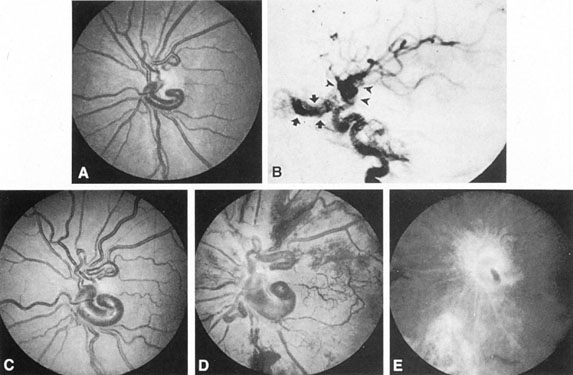

The detection of intracranial AVMs is facilitated by CT scanning and MRI (Fig. 10),88 but optimal management requires selective angiography89 that assesses the size and configuration of the mass, the number and location of feeding arteries, the flow characteristics and degree of steal from brain parenchyma, and the pattern of venous drainage.

Fig. 10. Neuroimaging of arteriovenous malformation. A: Coronal magnetic resonance imaging (MRI) (TR, 600 ms; TE, 20 ms) shows wedge-shaped vascular mass extending from the surface of the parietal cortex (white arrows) to the lateral ventricle (black arrows; asterisk, arterial feeder). B: Posteroanterior left arteriogram of the same lesion. C: Axial computed tomography scan with contrast enhancement. D: Axial MRI of a large arteriovenous malformation, first echo (TR, 2000 ms; TE, 20 ms). E: Second echo (TR, 2000 ms; TE, 90 ms). (From Smith HJ, Strother CM, Kikuchi Y, et al: MR imaging in the management of supratentorial intracranial AVMS. AJNR Am J Neuroradiol 9:225, 1988.)